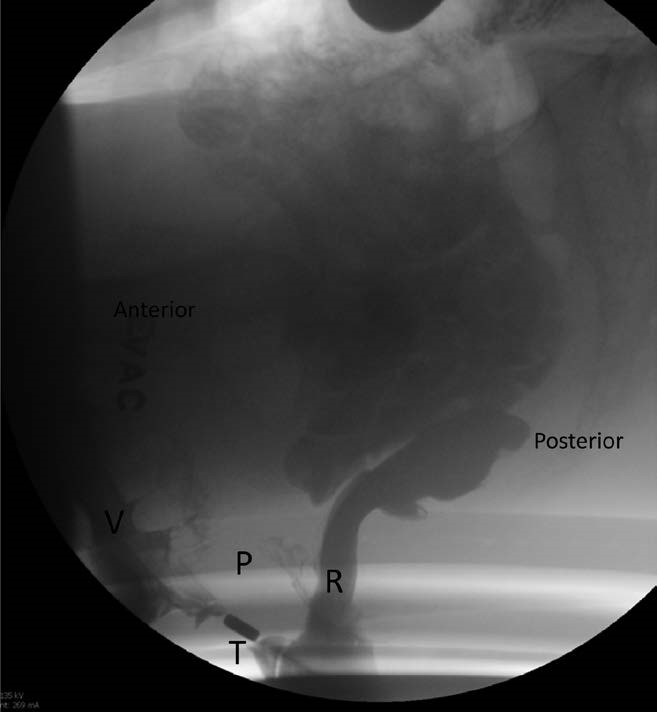

The anorectal angle is the angle between a line parallel to the posterior wall of the ampullary portion of the rectum and a line drawn along the anal canal (Fig. 7, Video 2) . This angle is observed during Kegel and at peak straining during defecography and compared to the angle at rest. The angle should become more acute during Kegel. In healthy individuals, the resting angle is approximately 85 to 96 degrees, which decreases by 10 to 15 degrees during Kegel and becomes more obtuse during straining in comparison to the angle at rest[41],[42] (Fig. 8). However, due to poor reproducibility, many radiologists do not measure the actual degree of change in the anorectal angle, and instead comment on whether the angle widens, narrows, or stays the same.[43]